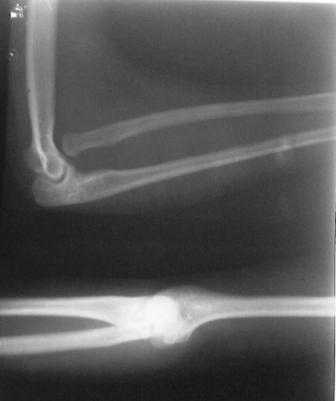

Уважаемые Коллеги! Добрый вечер! Обратилась девушка 18-лет, с жалобами на деформации обоих локтевых суставов, больна с рождения. Оба локтевых сустава в положении сгибания под углом 145гр., дальше разгибание нет за счет укороченных и натянутых м/тканей по передне-наружной поверхности л/сустава. Сгибание полное. но при сгибание предплечья супинируется а при разгибание пронируется,при фиксированным п/плечье ротационных движений нет.Со стороны костно-суставной системы других обл. я патологию не находил. В 2001 г. оперирована лев.рука в одном из центральном институте, со слов вывых был вправлен открыто и фиксация аппаратом Илизарова, после операции рука не сгибалась и ротационных движений не было, что очень ей мещало, после усиленных ЛФК наступило релюксация и движение стало лучше, т.е. как прежная. Фото и Р-снимки прилагается.

Снимки недостаточно информативны ( может быть не все сообщения пришли), рассматривать конфликт проксимального лучелоктевого сочленения невозможно без картинок дистального отдела. Глядя на представленные снимки и предъисторию открытого вправления с рецидивом вывиха, создается впечатление о диспропорции длины локтевой и лучевой костей, врожденном отсутствии аннулярной связи, удерживающей проксимальное лучелоктевое сочленение. Я бы посоветовал сделать снимки предплечья полной длины, включающих дистальное и

проксимальное л.л. сочленения и исходя из этого можно планировать вмешательство: как вариант при обнаружении диспропорции - укорачивающая

остеотомия луча с пластикой связки, если интраоперационно сохраняется тенденция к вывиху.